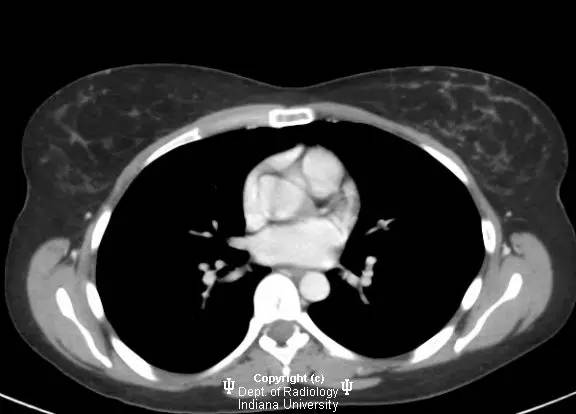

【影像学表现】

乳腺钼靶左乳腺内上象限见3.1cm卵圆形等密度肿块,部分界限清晰。超声见一2.5 x 2.1 x 1.9 cm混合回声肿块,宽大于高,边界清晰,后部回声增强。

浸润性导管癌

Invasive ductalcarcinoma

浸润性导管癌为乳腺癌的最常见类型(80%),有人认为由导管原位癌进展而来,病变可沿着真皮淋巴管播撒而导致皮肤增厚和乳头内陷。肿瘤多无症状,筛查时发现。女性多于中年好发。浸润性导管癌也是男性乳腺癌的最常见类型。淋巴结累及时提示预后不良。诊断多经超声引导下或立体定位活检。局限性病变治疗主要为手术,也可行放疗,化疗和激素治疗。